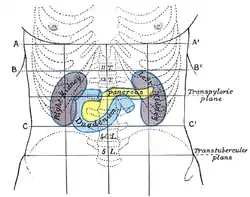

The ascending portion of the duodenum ascends on the left side of the aorta, as far as the level of the upper border of the second lumbar vertebra. At this point, it turns abruptly forward to merge with the jejunum, forming the duodenojejunal flexure. This forms the beginning of the jejunum.[3] The duodenojejunal flexure is surrounded by the suspensory muscle of the duodenum.[4]: 274 It is retroperitoneal, so is less mobile than the jejunum that comes after it, helping to stabilise the jejunum.[5]

The duodenojejunal flexure lies in front of the left psoas major muscle, the left renal artery, and the left renal vein. It is covered in front, and partly at the sides, by peritoneum continuous with the left portion of the mesentery.